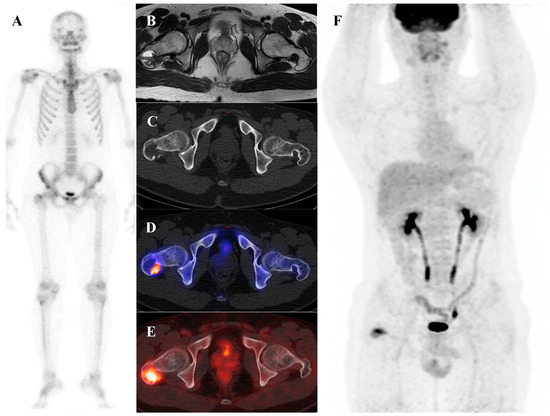

Clinical, Radiological, and Pathological Features of Intraosseous Hibernoma: A Systematic Review of Case Reports and Case Series

Intraosseous hibernoma (IOH) is a rare benign tumor composed of brown adipose tissue within the bone, frequently mimicking metastatic lesions and leading to diagnostic challenges. This systematic review aimed to consolidate and analyze all published IOH cases to improve recognition and inform management. [...] Read more.

Intraosseous hibernoma (IOH) is a rare benign tumor composed of brown adipose tissue within the bone, frequently mimicking metastatic lesions and leading to diagnostic challenges. This systematic review aimed to consolidate and analyze all published IOH cases to improve recognition and inform management. A comprehensive literature search was conducted in PubMed, Web of Science, Scopus, Google Scholar, and the Cochrane Library from database inception to March 2025. Studies were eligible for inclusion if they reported histopathologically confirmed cases of intraosseous hibernoma (IOH) in human patients. A total of 62 cases from 30 studies were included. The mean age was 59.2 years, with a female predominance. Lesions were most frequently located in the pelvis and spine and were typically identified incidentally during cancer staging or imaging performed for unrelated indications. Imaging often revealed sclerotic patterns on computed tomography (CT), hyperintense signals on magnetic resonance imaging (MRI) T2-weighted and short tau inversion recovery (STIR) sequences, and mild to moderate uptake on 18F-fluorodeoxyglucose positron emission tomography/computed tomography (18F-FDG PET/CT). Immunohistochemistry consistently showed S100 protein positivity. Most patients underwent biopsy and were managed conservatively, with no cases of malignant transformation reported. IOH is a benign entity with distinctive radiologic and immunohistochemical features that may mimic malignancy. Awareness of its presentation can reduce misdiagnosis and unnecessary interventions, supporting biopsy-based confirmation and conservative management in most cases. Full article